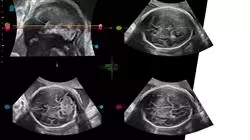

Il notevole aumento nell'ultimo decennio dei problemi legati alla gravidanza rappresenta una tematica che preoccupa i professionisti in Ginecologia e Ostetricia. Tuttavia, gli studi condotti in quest'ambito della Medicina hanno permesso di individuare concretamente molte delle cause che provocano aborti e malformazioni, aiutandoli a prevenirli attraverso un’assistenza clinica specializzata. Per questo motivo, l'importanza che ha assunto la Medicina Materno-Fetale è fondamentale, manifestandosi nel controllo completo durante la gravidanza attraverso esami diagnostici sempre più specifici, incentrati anche sulle caratteristiche fisiologiche o congenite della madre.

Per i motivi appena citati, TECH ha ritenuto necessario lo sviluppo di un programma che raccolga le informazioni più avanzate al riguardo, permettendo al professionista di aggiornarsi sulle novità della patologia Materno-Fetale attraverso un corso specifico. A tal fine, lo studente disporrà di 450 ore del miglior contenuto teorico, pratico e integrativo, preparato da un'équipe di specialisti in Ginecologia e Ostetricia con anni di esperienza nel settore. Il professionista sarà in grado di approfondire i modelli diagnostici terapeutici più innovativi da trattare, come la patologia placentare e la restrizione della crescita fetale. Inoltre, lavorerà intensamente al perfezionamento delle sue capacità cliniche attraverso la risoluzione simulata di decine di casi reali legati, ad esempio, ad anomalie del cordone ombelicale, infezioni congenite, malattie endocrinologhe, ecc.

Tieniti aggiornato sugli ultimi progressi della medicina materno-fetale

Questo Esperto Universitario in Medicina Materno-Fetale 100% online ti permetterà di approfondire la patologia materno-fetale e di lavorare per perfezionare le tue abilità cliniche attraverso la risoluzione simulata di più casi reali relativi a varie patologie, dalle anomalie del cordone ombelicale a malattie endocrine. Progettato da un team di esperti di ostetricia e ginecologia con decenni di esperienza nel settore, il programma include ampi contenuti teorici, pratici e aggiuntivi ed è disponibile per il download su qualsiasi dispositivo dotato di connessione Internet.